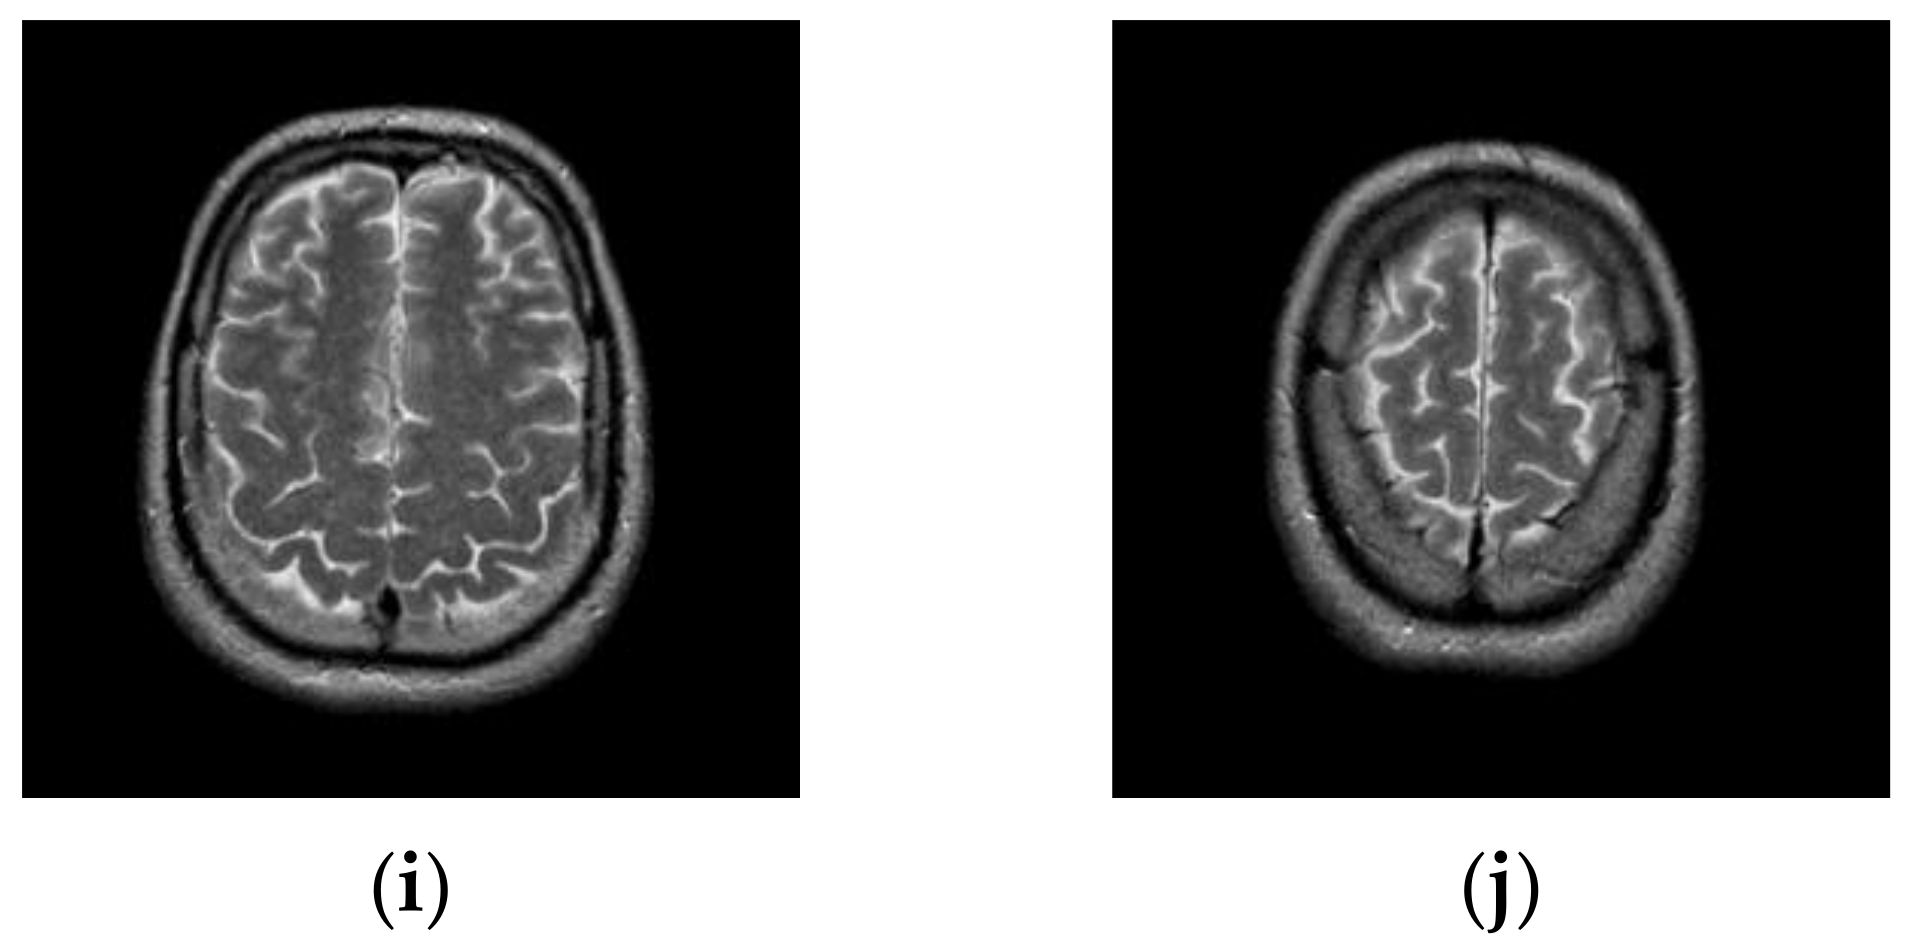

Transaxial MR-T2 brain images with various slices downloaded from “The Whole Brain Atlas” of Harvard Medical School (http://www.med.harvard.edu/aanlib/home.html, accessed on 17 May 2021) were used in the segmentation experiments. Because space is limited, the ten brain slices #022~#112 displayed in Figure 9 were chosen to demonstrate the performance of our proposed algorithm. Parameters for the proposed algorithm are listed in Table 1. All experiments were performed on a computer with Intel(R) Core(TM) i7-7500U CPU, 2.70 GHz, 8GB RAM, Windows 10 using MATLAB 8.1.0.604 (R2013a).

Figure 9.

MR-T2 brain slices: (a) slice #022, (b) slice #032, (c) slice #042, (d) slice #052, (e) slice #062, (f) slice #072, (g) slice #082, (h) slice #092, (i) slice #102, (j) slice #112.